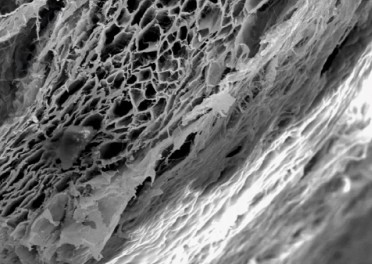

Due to its porous and fibered microstructure, the membrane readily absorbs fluids, adheres to the surrounding tissues, and provides a barrier that guides bone and tissue regeneration.